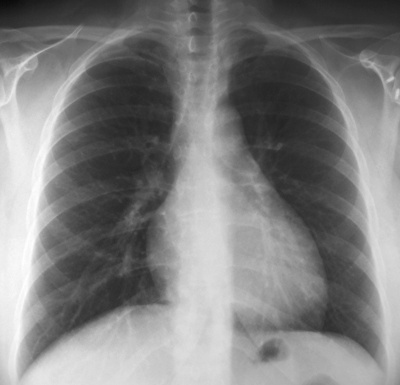

Las imágenes de rayos X son en blanco y negro. Las partes densas del organismo, que bloquean el paso del haz de rayos X a través del organismo, como el corazón y los huesos, se ven de color blanco en la imagen. Las partes huecas del cuerpo, como los pulmones, permiten que el haz de rayos X los atraviese y aparecen en negro.

Las radiografías están a cargo de un radiólogo o técnico en rayos X. En general, se toman dos radiografías: una desde la parte posterior de la espalda si el niño es lo suficientemente grande como para quedarse parado para la radiografía y otra desde el costado. En el caso de los niños más pequeños se toma una imagen del frente del tórax así como del costado.